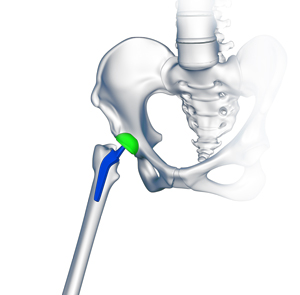

The hip is a ball-and-socket joint made up of the head of the thigh bone or femur, that acts as the ball, and the rounded socket of the hip bone or acetabulum. The neck of the femur is the region just below the ball of the hip joint.

The bespoke hip implant includes a femoral component with a patient-specific neck, an acetabular cup, and a biocompatible plastic liner. The femoral head can be made of either ceramic or cobalt chrome.

The custom implant is designed such that its shape matches the patient’s bone defect/bone geometry and can adapt to the human body.